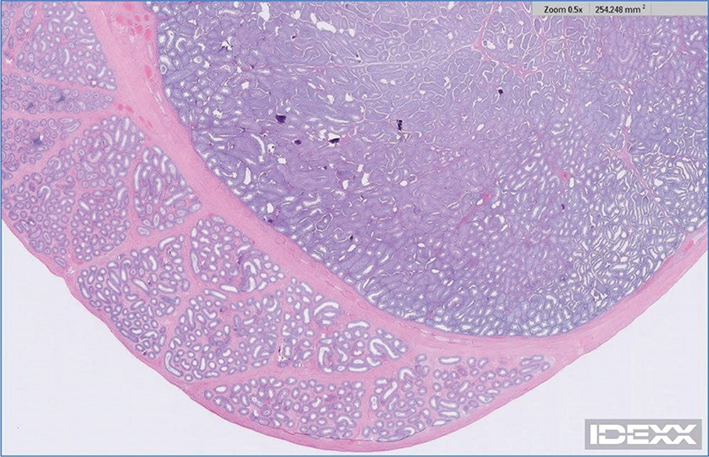

Case 1: A 3½ year, intact male Treeing Walker Coonhound, was presented for ultrasonographic evaluation of the abdomen and testes due to weight loss and polyphagia in July of 2021. Semen had not been evaluated, but the dog had sired a litter in 2020. Left testis appeared normal and had a coarse medium echogenicity throughout; right testis contained hyperechoic foci that were slightly larger than typical testicular microliths observed in human beings but were identical to TM in all other aspects (Figure 1). Other findings on abdominal ultrasonography included a complex cystic structure in the right kidney. Ultrasonography of the testes was repeated in October of 2021 and July of 2022, with no changes noted from the original ultrasonography. In October of 2022, the dog was castrated, due to concern about testicular microlithiasis, a couple of episodes of prostatitis, and retirement from breeding. Right testis was submitted for histopathology; 2 discrete and relatively small foci of intratubular mineralization accompanied by surrounding fibrosis were noted. In these foci, aggregates of fragmented basophilic material, interpreted to represent mineralization, were present within shrunken seminiferous tubules surrounded by a moderate amount of fibrosis (Figures 24) without associated inflammation.

Figure 2.

Figure 2. Testicular histopathology (low magnification) of Case 1

Figure 3.

Figure 3. Testicular histopathology (medium magnification) of Case 1